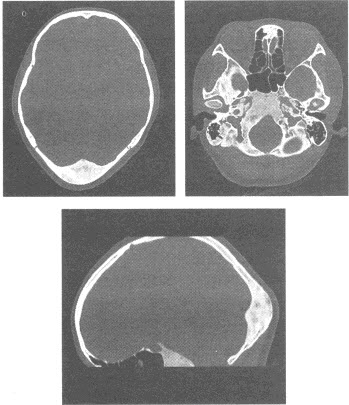

患者,女,65岁。左侧肢体偏瘫,言语不清2天入院,曾有高血压病史多年。影像学检查如下图。

(单选题)根据该患者的影像学表现,栓塞部位可能位于()

A:右侧椎动脉

B:基底动脉

C:右侧颈内动脉

D:右侧大脑中动脉

E:右侧大脑前动脉

F:右侧大脑后动脉